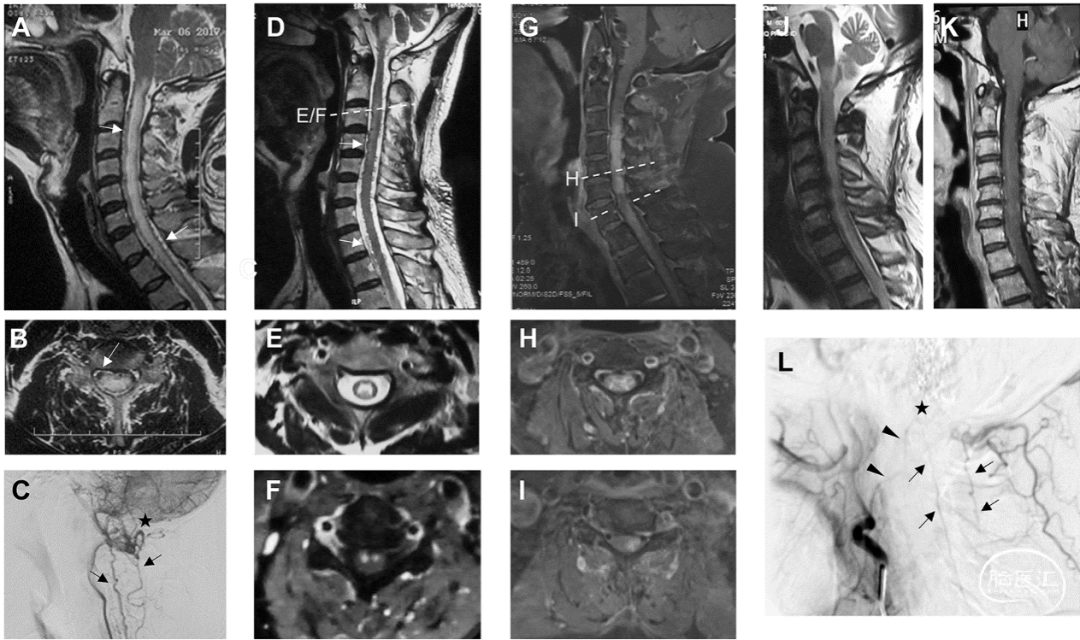

所有9名复发患者(13.8%)均为硬膜动静脉瘘,对应的两种复发模式如图5所示。第一种是血管再通(图5A-L)。共有8名患者在第一次治疗时接受了经动脉栓塞。5名患者使用Onyx作为栓塞材料,3名患者因栓塞再通而再次手术。栓塞组的复发率高于手术组(表3,p=0.007)。Kaplan-Meier分析表明,栓塞组的复发风险增加了11倍(中位复发时间=34个月,p<0.0001,图6A)。另一种复发模式是新生对侧供血动静脉瘘。有4例患者(手术3例,栓塞1例)出现这类型复发,其引流静脉可以与首次患病时相同(图5O/S,n=3)或不同(图5I/J,n=1)。其余复发患者(1例手术,2例栓塞)因首次造影资料缺失无法准确判断原因。大部分复发患者(8/9,88.9%)在我院接受显微手术二次治疗。